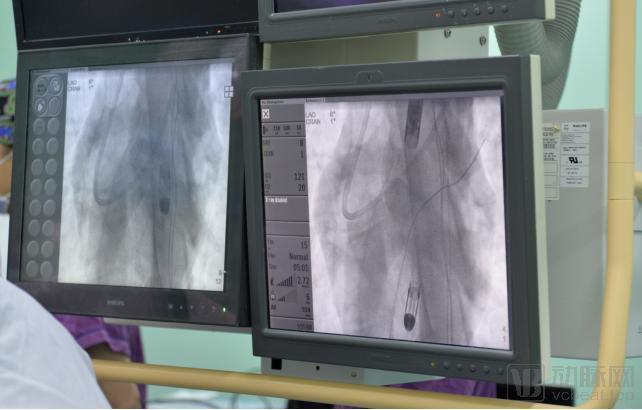

2021年1月 , 在国家心血管病中心心血管在体实验及评价中心发生了一件影响中国人工心脏行业的盛事:中国医学科学院阜外医院胡盛寿院士带领团队成功实施了国内自主研发的经皮置入心室辅助装置(pVAD , 又称介入式人工心脏)的动物实验 。 实验数据显示 , 术后动物恢复良好 , 各项生理指征正常 。 此次动物实验是国内公开报道的自主研发pVAD的首次成功实施 , 不仅打破了海外技术垄断的局面 , 弥补了我国在这一领域的技术空白 , 还为我国自主研发心血管高端医疗器械注入了活力 。

体外流体实验是指在动物实验之前进行的体外模拟 。 例如 , 溶血实验中 , 研发团队将动物血液导入实验装置后把pVAD放入实验装置 , 以此模拟动物心脏的运行过程及运行环境 。 在实验中 , 研发团队可利用多种体外仪器和设备检测血压、血流、血液指标等信息 , 并依据此数据评估、测算pVAD将在动物实验中遇到的实际负荷、意外情况及极限工况 。 通过以上测算 , 即可评估pVAD的功能性及安全可靠性是否被允许置入动物或人体内 。